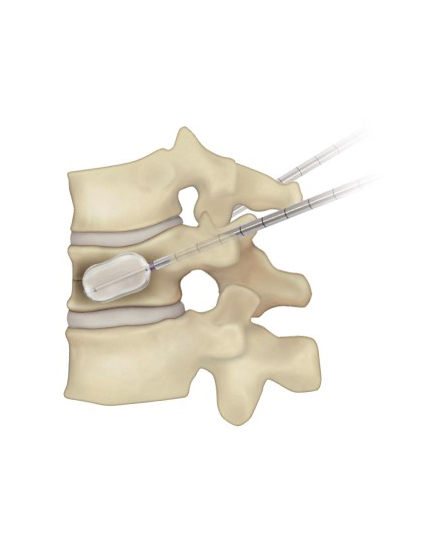

経皮的椎体形成術 BKP(ビーケーピー)

適応となる疾患:骨粗鬆症性椎体骨折、転移性脊椎腫瘍

骨粗鬆症による背骨の骨折や転移性脊椎腫瘍(がんの背骨への転移)による病的骨折に対して世界中で行われている低侵襲な手術法です。日本では2011年に保険適用になり行われています。全身麻酔をして背中の約5mmの傷2カ所から細い針を骨折椎体に挿入します。その針を介して風船(Balloon)を骨折椎体内に設置し、ゆっくりと潰れた骨を整復・復元します。整復後に除去した風船のスペースに骨セメントを注入して、骨折を人工的に接合します。手術は約1時間程度で、手術直後から痛みが軽減することが多く、翌日より起立・歩行を開始します。入院期間は通常約3~7日程度になります。